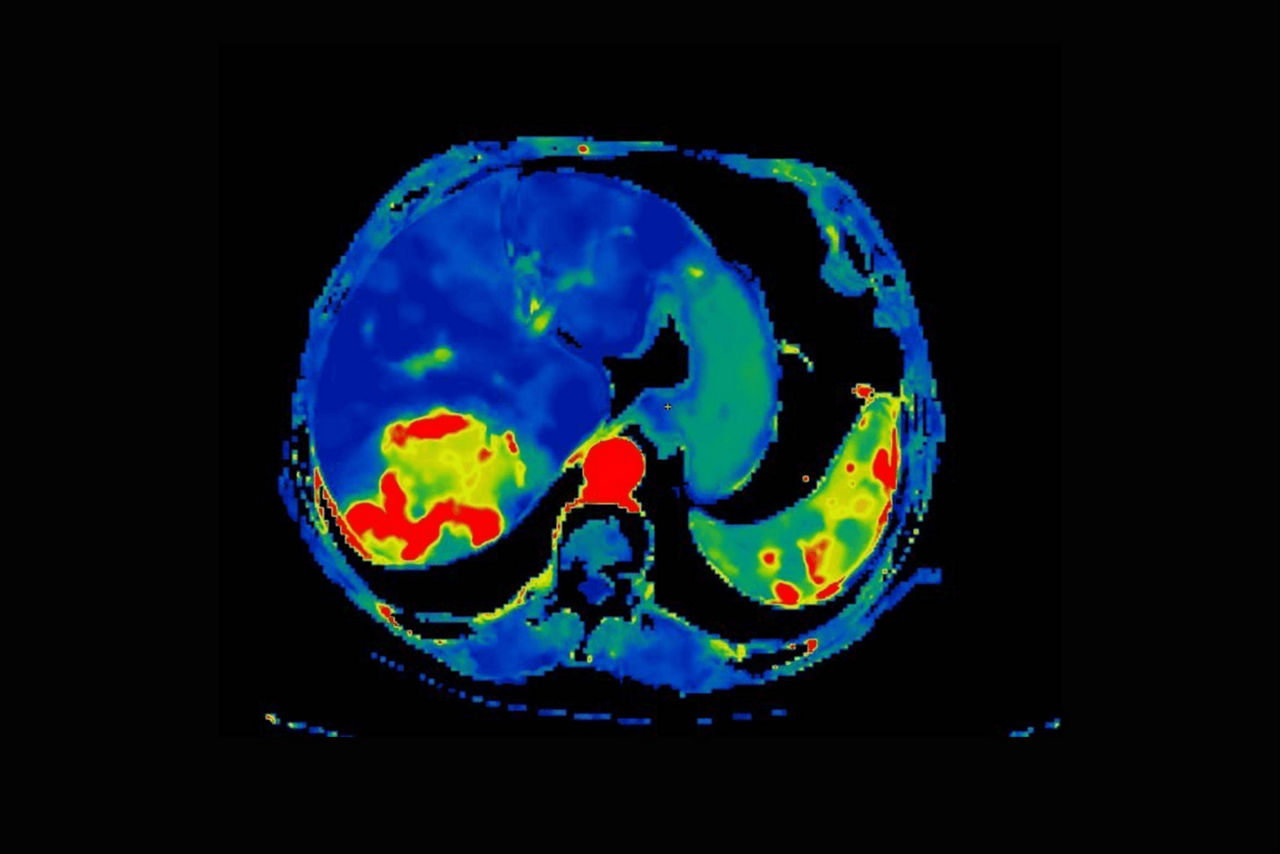

Body perfusion

Optimized protocols for kidney, soft tissue, liver perfusion and other body tumors

CT Body Tumor Protocol

• Automatically produces functional maps once the user selects an artery using a simple and intuitive workflow

• Leverages most of the advanced algorithm settings that are part of the Brain Stroke protocol

• Optimized protocols for pancreas, prostate, kidney, soft tissue, spleen, bone and liver perfusion

• CT Non-Rigid Registration: Fully automated protocols used for dynamic body acquisitions to register data for use in perfusion analysis